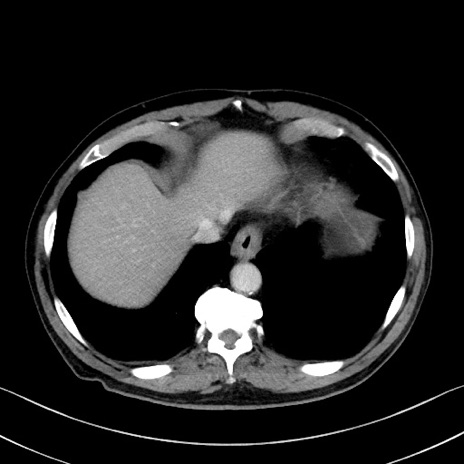

症例35(横断像)

【症例】70歳代 男性

【主訴】腹部膨満、嘔吐

【現病歴】昨日より腹部膨満感出現。本日増悪し、仙痛出現。嘔吐あり、受診。

【既往歴】糖尿病、胆摘後

【身体所見】BP 149/80mmHg、HR 74/min、BT 35.9℃、腹部:膨満、軟、圧痛なし。腸雑音減弱あり。上腹部正中切開瘢痕あり。

【データ】WBC 13500、CRP 1.72